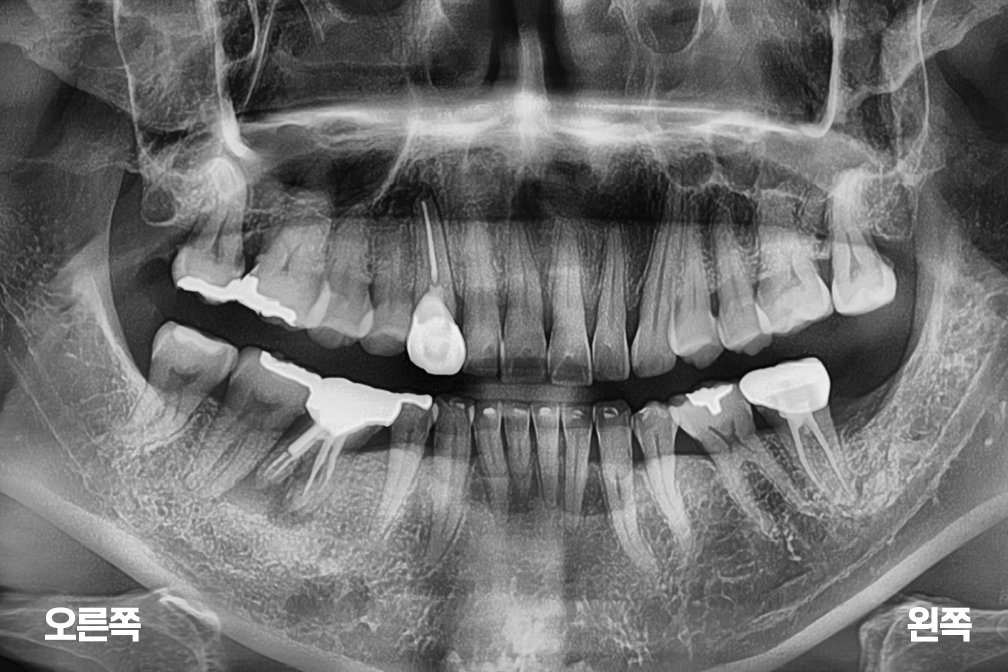

어금니 임플란트

After 2026년 1월 16일